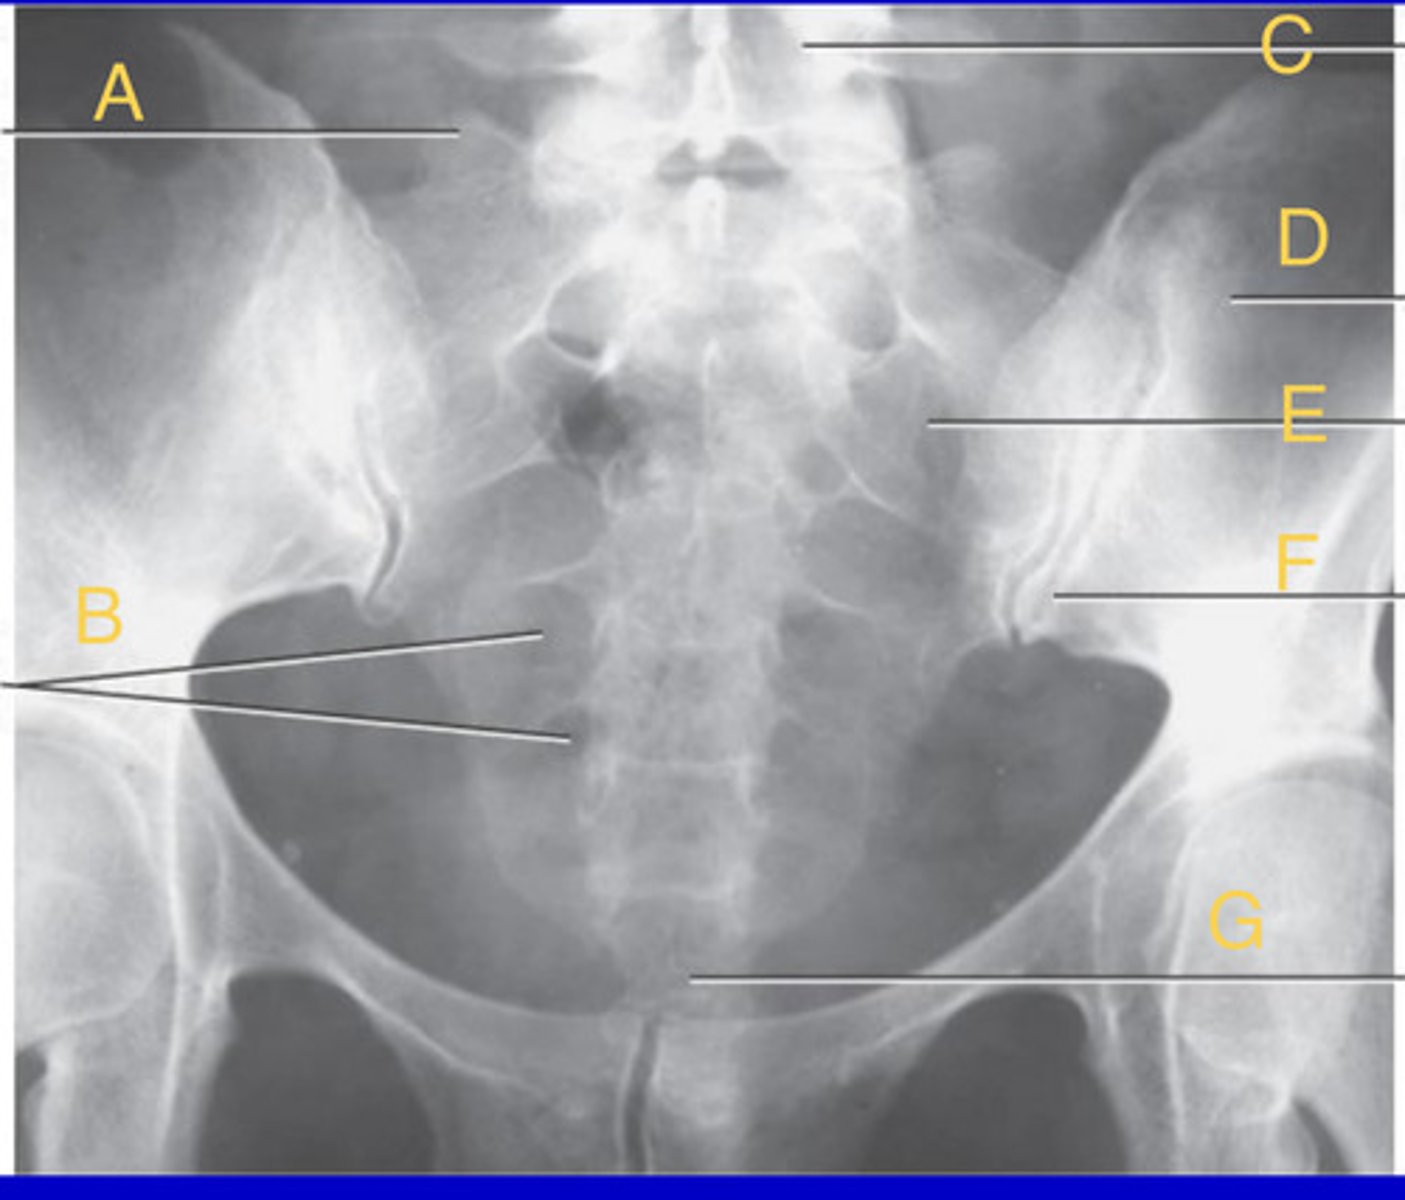

R sacroiliac joint

A.

L1 transverse process

B.

L2 spinous process

C.

L3-4 intervertebral space

D.

Ala of sacrum

E.

AP L spine

What position?